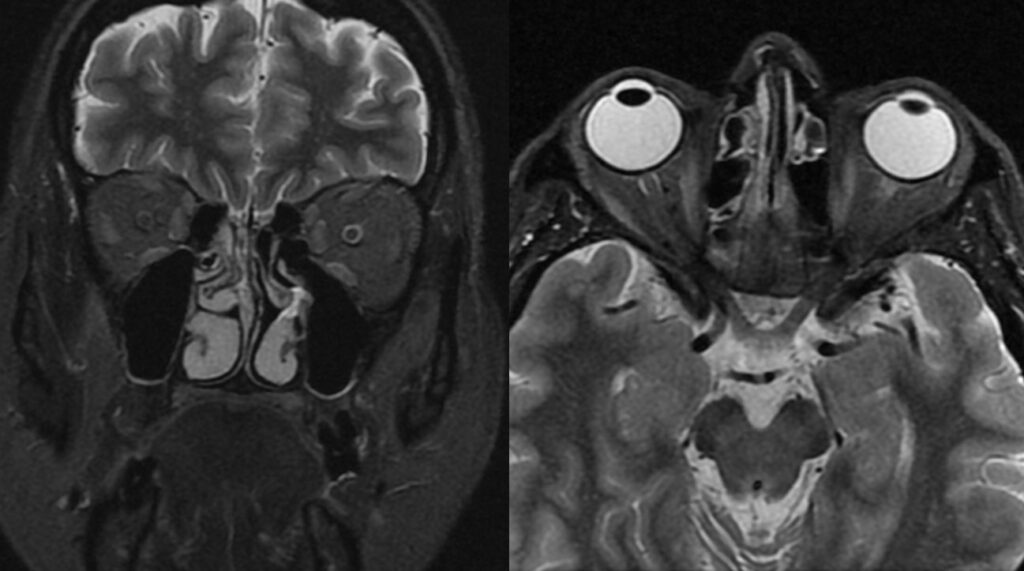

Εικόνα 1: Εικόνες βάρους Τ2 STIR (με καταστολή του λίπους) οφθαλμικών κόγχων σε (α) στεφανιαίο και (β) εγκάρσιο επίπεδο.